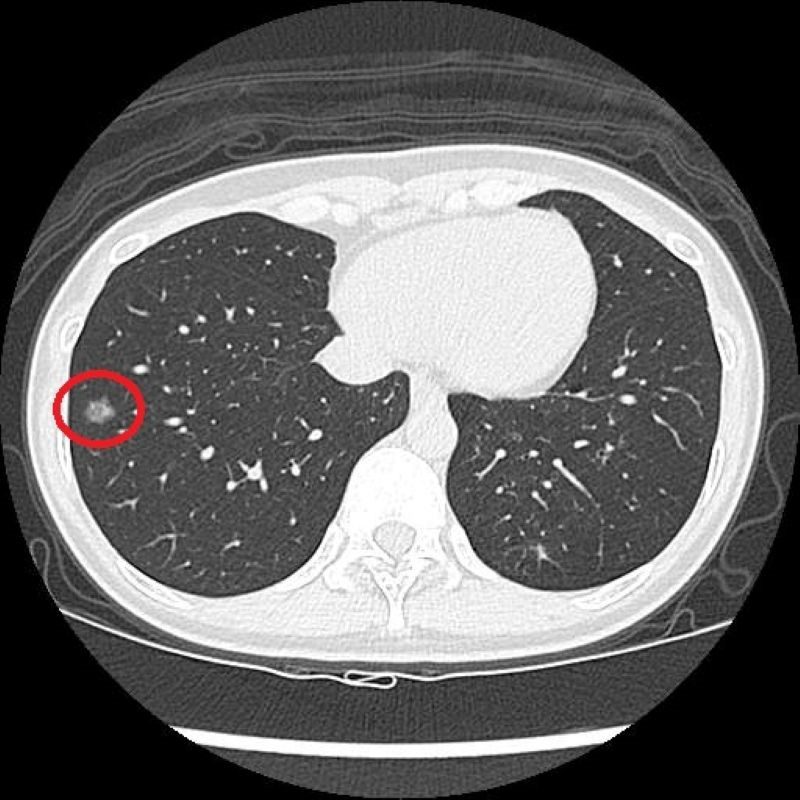

過去有長期的吸菸史的41歲的陳小姐,在醫療團隊的協助下戒菸近兩年,雖然沒有任何不適,但仍定期留意自身健康。因符合政府公費「低劑量電腦斷層(LDCT)」篩檢條件,她依建議至台北慈濟醫院接受檢查,卻意外發現右肺有一顆約1.2公分的毛玻璃結節,被轉診至胸腔外科門診,由洪嘉聰醫師進行單孔胸腔鏡微創手術切除病灶,術後病理檢查確診為肺腺癌第一期,目前定期回診追蹤中。

早期肺癌難察覺 LDCT揪出病灶 20260115 1LDCT檢查顯示,陳小姐右側肺部有一1.2公分大的毛玻璃結節。